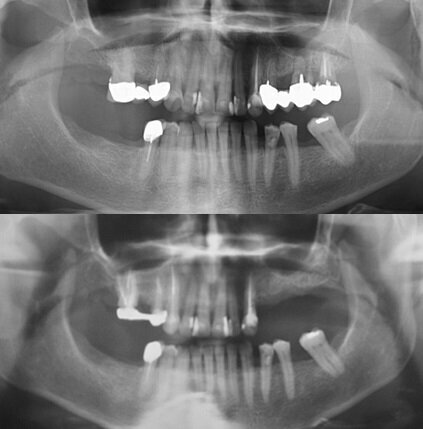

La paziente, di 66 anni non fumatrice, si è presentata all’attenzione del chirurgo richiedendo la riabilitazione del mascellare superiore sinistro, privo degli elementi da 2.4 a 2.7 (Fig. 1). Dopo valutazione clinica e radiografica, anche attraverso CBCT, alla paziente è stato proposto un piano di riabilitazione basato sull’esecuzione di un rialzo di seno ed il contestuale inserimento di tre impianti osteointegrati. La paziente ha fornito il proprio consenso informato al trattamento.

Fig. 1_La paziente presenta un’edentulia nel settore superiore posteriore sinistro (figura in basso) conseguente all’estrazione, avvenuta 2 anni prima, di alcuni elementi a supporto di un ponte da 2.4 a 2.7 (figura in alto, radiografia pregressa conferita dalla paziente).